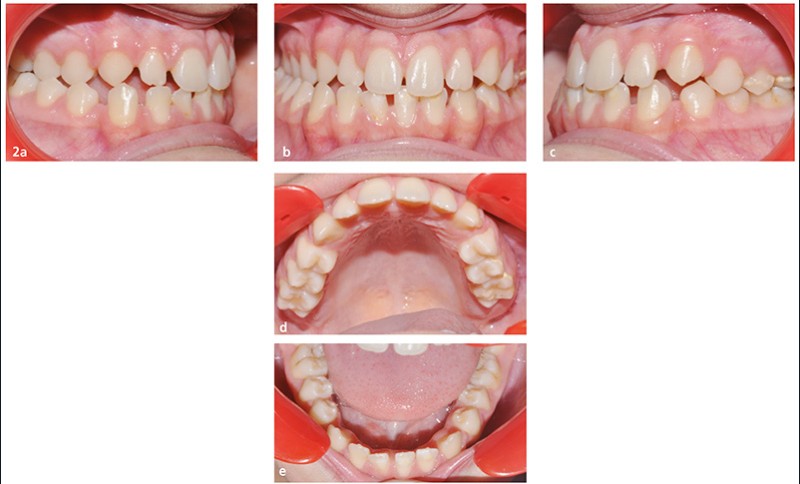

Il s’agit d’une adolescente de 13 ans présentant une latérognathie mandibulaire modérée.

Articulé inversé secteur 1/4 commençant dès 12/42 jusqu’à 15/45 (fig. 1 et 2).

Dysfonction linguale majeure. Pas de trouble de la ventilation nasale.

L’asymétrie squelettique n’entraîne pas de disgrâce faciale majeure.